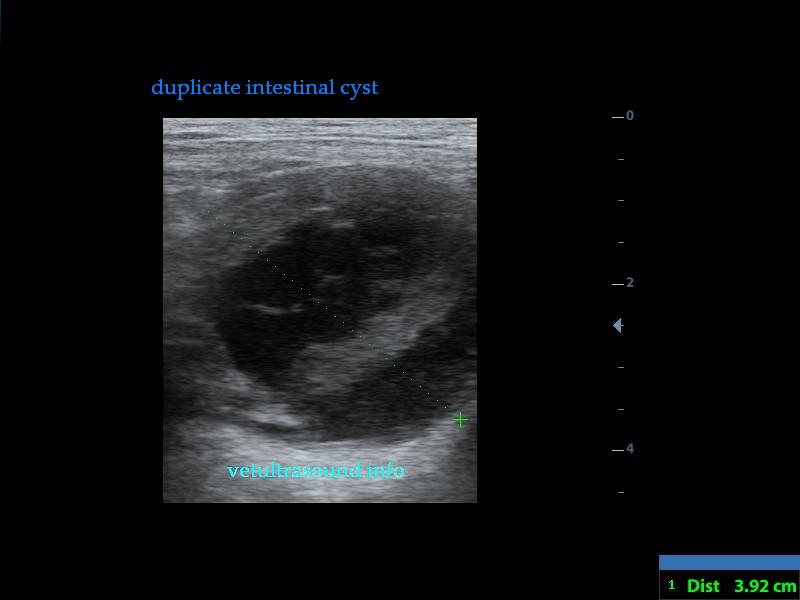

Findings: There was a mild enlargement of the mesenteric lymphnodes(pic3). In a small segment of the small intestine a cyst was noted which was attached to the intestinal wall(pic2.3). There were also dilated intestinal loops before the cyst due to the narrowed intestinal lumen. No free fluid was noted. There was a mild increase of the mesenteric fat arround the cyst.

Diagnose: Duplicate intestinal cyst. I am attaching a link of a case report from the Canadian Veterinary Journal.

Διάγνωση: Δίλοβος εντερική κύστη, στην εικόνα από το χειρουργείο φαίνεται η κύστη ανοιγμένη πλέον. Συχνά αποτελούν τυχαία ευρήματα,διότι πολλές φορές αν δεν επιπλακούν ή δεν επηρεάσουν χωροκατακτητικά την κινητικότητα του εντέρου δεν δίνουν άλλα συμπτώματα. Η παθοφυσιολογία τους συνήθως είναι εμβρυικής αιτιολογίας.